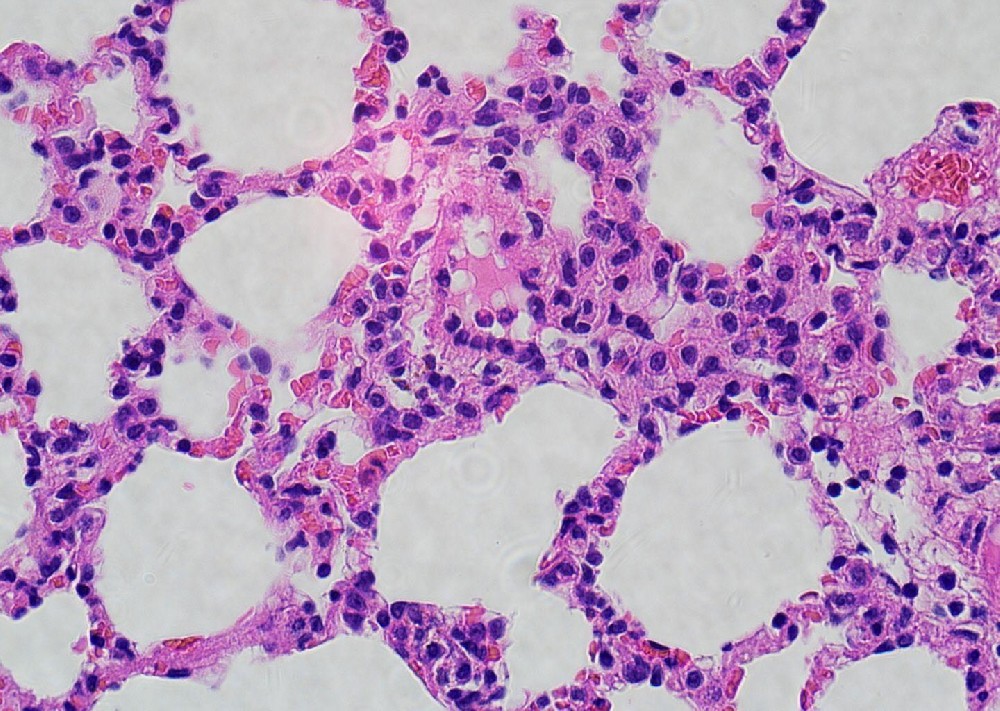

(一)实验目的通过苏木素(碱性染料)和伊红(酸性染料)对组织切片进行染色,使细胞核、细胞质呈现不同颜色,清晰显示组织细胞的形态结构、排列方式,为病理诊断提供基础依据。(二)实验材料1. 样本:已烤好的病理···

(一)实验目的将新鲜组织标本制成薄而连续的石蜡切片,为HE染色、免疫组化等后续病理检测提供优质样本,便于显微镜下观察组织形态结构及病理变化。(二)实验材料1. 样本:新鲜动物组织或人体穿刺/手术标本;2. 试剂···

1、取材:新鲜组织固定于10%中性福尔马林24h以上。将组织从固定液取出在通风橱内用手术刀将目的部位组织修平整,将修切好的组织放入写有对应编号的脱水盒内。2、脱水:将脱水盒放进吊篮里于脱水机内依次梯度酒精进行···